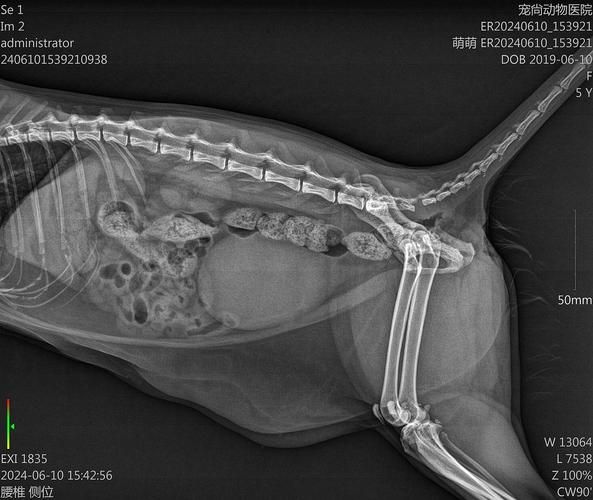

猫咪腰椎受伤凹陷,主人的担忧可以理解。四个月大的猫咪因意外导致腰椎受损,出现骨裂和椎间间隙增大,尽管大小便正常,但后腿无力和腰部塌陷,这无疑给主人带来了巨大的压力。在猫咪腰椎损伤初期,限制运动是至关重要的。建议在3-6个月内避免剧烈活动,尤其是跳跃和攀爬高处,以防止进一步损伤。同时,为缓解疼痛,可以短期给予适量的止痛药,但剂量必须根据猫咪的体重精确调整。在抱起猫咪时,需要特别注意避免对其腰部造成压力。推荐采用从下方平行托起的方式抱猫,这样可以有效减轻腰部负担,避免直接抱起而引起疼痛。